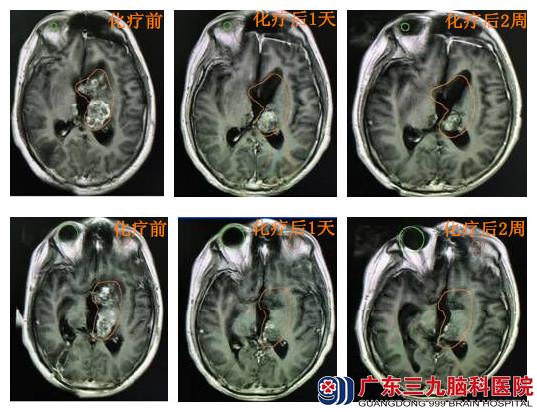

陈某,男,20岁,因 “复发生殖细胞肿瘤术后1月余,VP分流术后5天”于2015年1月入院,一个月后出院。患者2008年4月无明显诱因出现反复头痛头晕,伴恶心呕吐、全身乏力,至广州某三甲医院就诊,头颅MR示:松果体区占位性病变,考虑生殖细胞瘤可能性大;双侧侧脑室及三脑室梗阻性脑积水。2008年4月21日,行“肿瘤活检+第三脑室造瘘术”,一周后行伽马刀治疗。术后病理:恶性肿瘤,生殖细胞瘤或松果体细胞肿瘤。2014年11月初,患者再次出现阵发性头痛,伴头晕、恶心呕吐,呈进行性加重,偶有胡言乱语。入当地医院就诊,于12月2日行“左侧脑室入路第三脑室肿瘤切除术”,术后病理:胚胎性癌;成熟型囊性畸胎瘤。2015年1月2日复查头颅CT提示肿瘤复发,梗阻性脑积水,1月8日行脑室腹腔分流术,术后转入广东三九脑科医院肿瘤综合治疗中心继续治疗。查体:神志清,精神萎靡,反应迟钝,气管切开,无法言语。双侧瞳孔直径约3.0mm,光反射迟钝。左侧肢体肌力IV级,右侧肢体肌力V-级,肌张力正常。头部、腹部伤口愈合可,未拆线。于2015年1月15日、2月5日行2程BEP化疗,方案为:顺铂30mg d1-5,依托泊苷0.1g d1-5,博来霉素1.5万u d1、5。复查头颅MR示肿瘤较前明显缩小,2程化疗后出院调理。3月份返院,患者病情稳定,生活完全自理,现继续行辅助化疗。